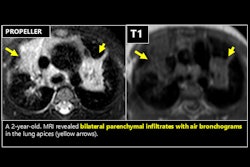

Patients with ILD are at increased risk of lung cancer, but finding the disease can be tricky due to background fibrosis – which can then lead to diagnostic delays, the group explained. Since research on lung cancer in ILD is scarce, the investigators conducted a study that analyzed delayed lung cancer diagnoses in ILD patients, tracking tumor stage at diagnosis, growth rates, treatment regimens, and outcomes.

Their study included 77 patients with concurrent ILD and lung cancer. A thoracic radiologist reviewed chest CTs for the following: earliest visible and reportable lesion time, when a lesion was first deemed suspicious, and the lesion's growth rate; the team also analyzed tumor staging, treatment regimens, and outcomes.

Schnitzler's group found that in 47% of the 77 cases, diagnosis was delayed, with an average delay of 3.4 years. These diagnostically delayed cases had a mean annual growth rate of 293% and a mean doubling time of 3.3 years, according to the team, which also noted that median patient survival time was 1,269 days for cancers that were found early compared with a median patient survival time of 867 days for cancers that were diagnostically delayed -- although this difference was not statistically significant.